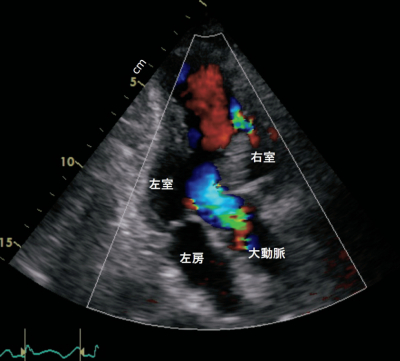

血液所見:赤血球 521万、Hb 15.6 g/dL、白血球 12,200、血小板 16万。血液生化学所見:AST 560 U/L、ALT 164 U/L、LD 826 U/L (基準 120~245)、CK 1,564 U/L (基準 30~140) 、尿素窒素 27 mg/dL、クレアチニン 0.8 mg/dL。CRP 0.6 mg/dL。心電図及び心エコー図を別に示す。

診断はどれか。2つ選べ。

a. 乳頭筋断裂

b. 急性心筋梗塞

c. 心室中隔穿孔